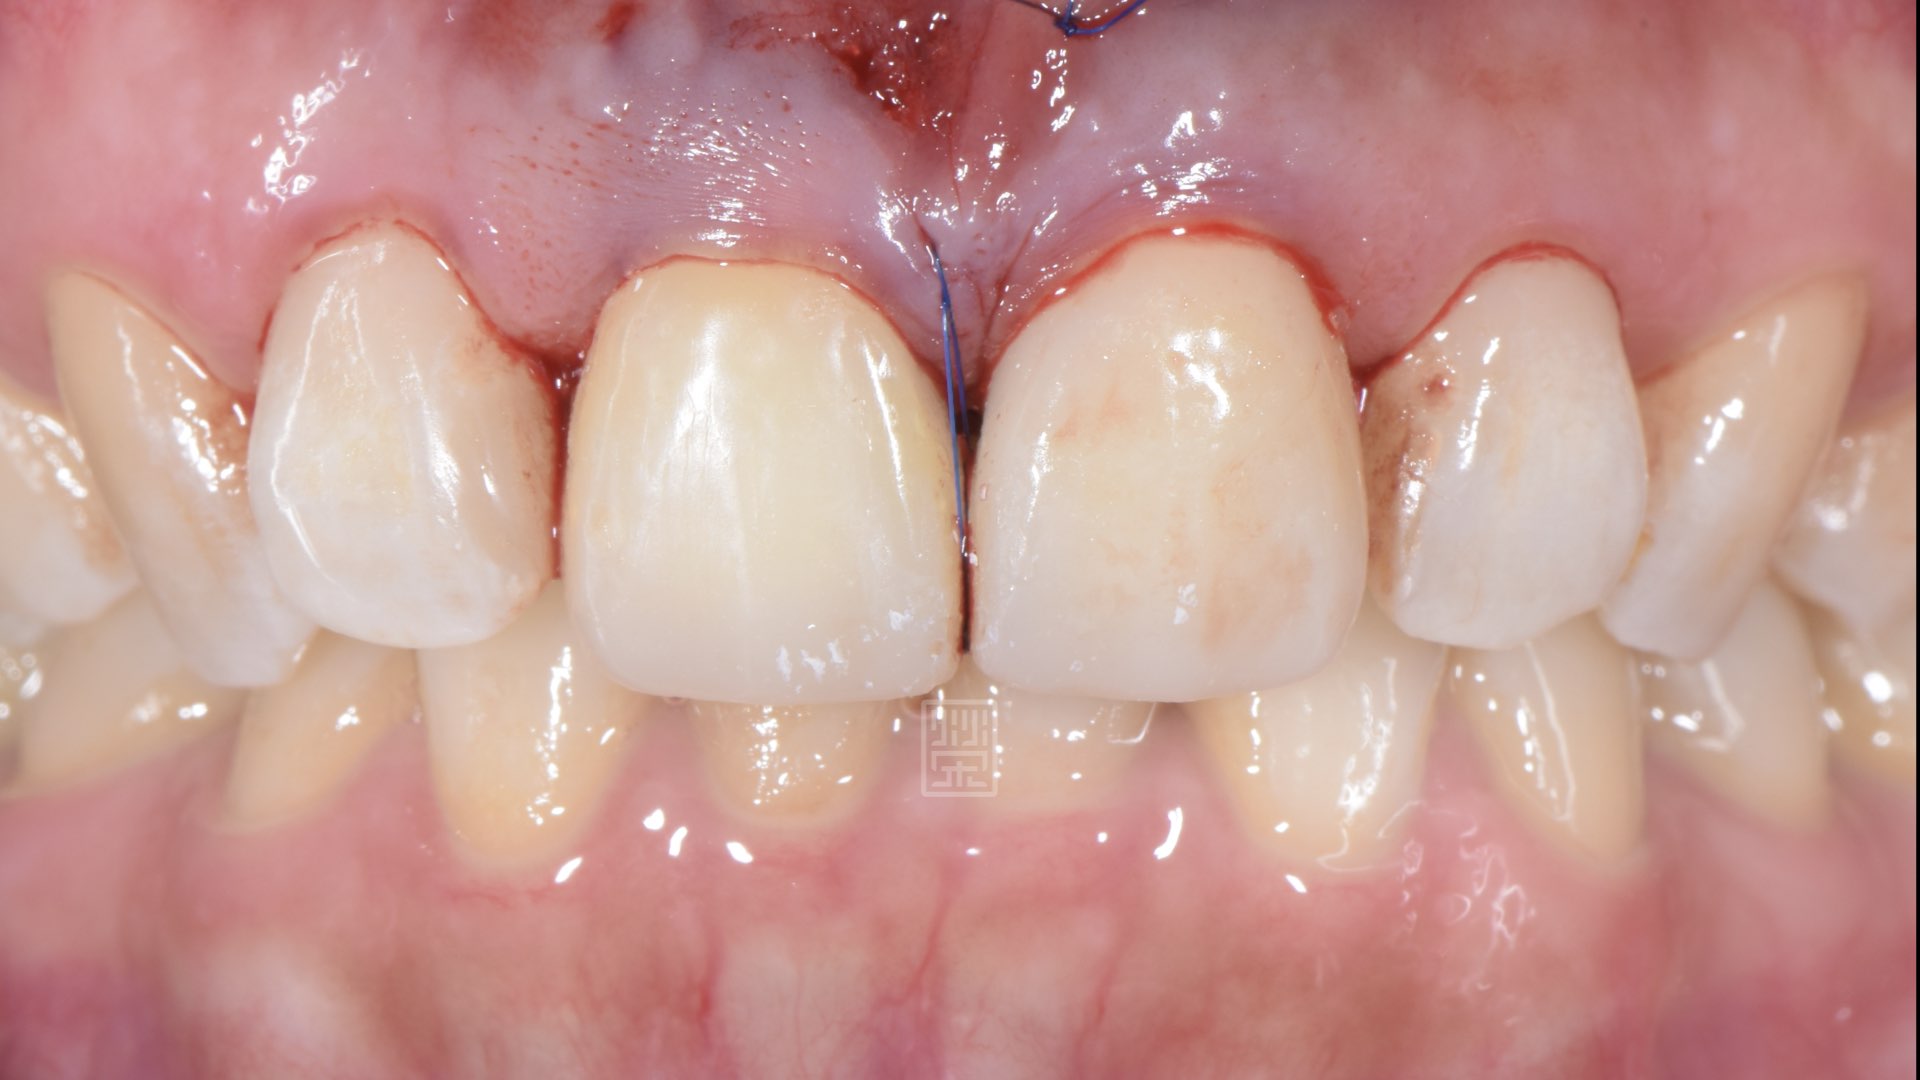

將黑三角縫再打開,以準備牙齦手術填補空間

牙齦手術,將黑三角縫填補